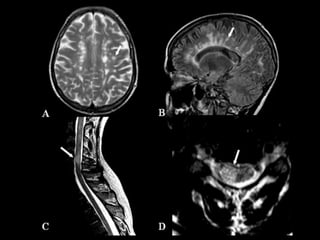

Esclerose Múltipla    A esclerose múltipla (EM) é uma doença desmielinizante inflamatória crônica, auto-imune, confinada ao sistema nervoso central (SNC). As proteínas da bainha de mielina constituem os alvos das agressões.